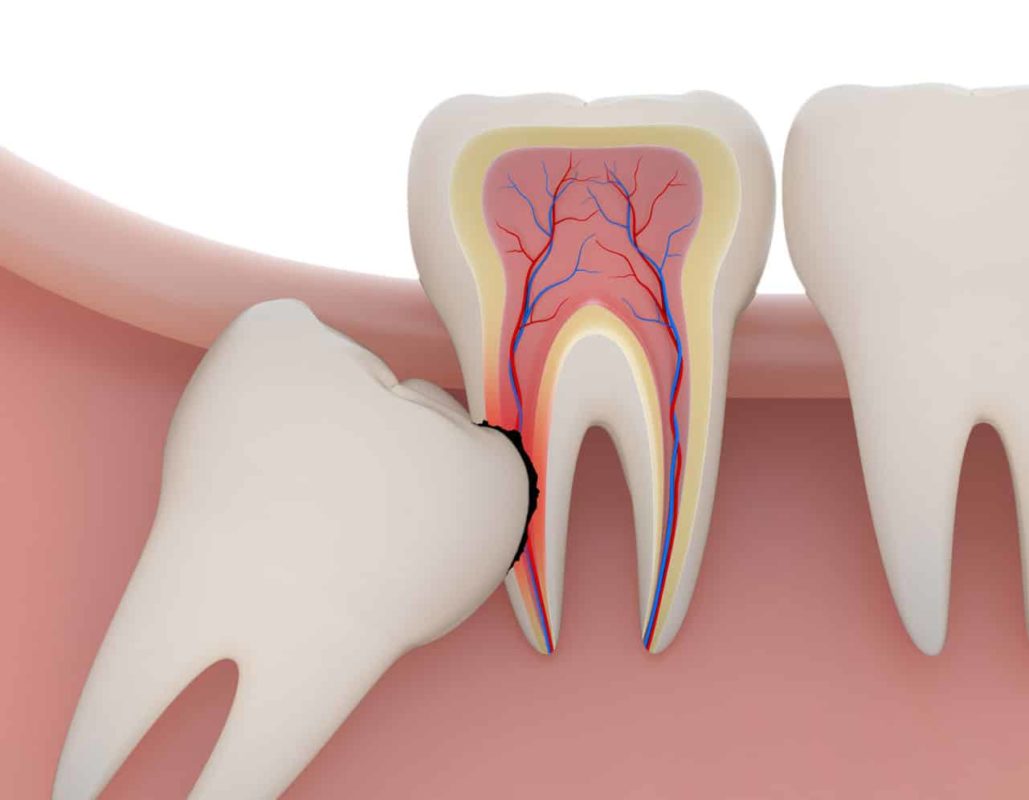

Então o siso pode interferir no alinhamento da arcada dentária?

Sim. Como ele nasce mais tarde, existe a possibilidade de o paciente não ter espaço suficiente na boca para acomodá-lo. Aí, ele pode empurrar os dentes que já estão ali, entortando-os. Mas, lembre-se: cada caso é um caso.